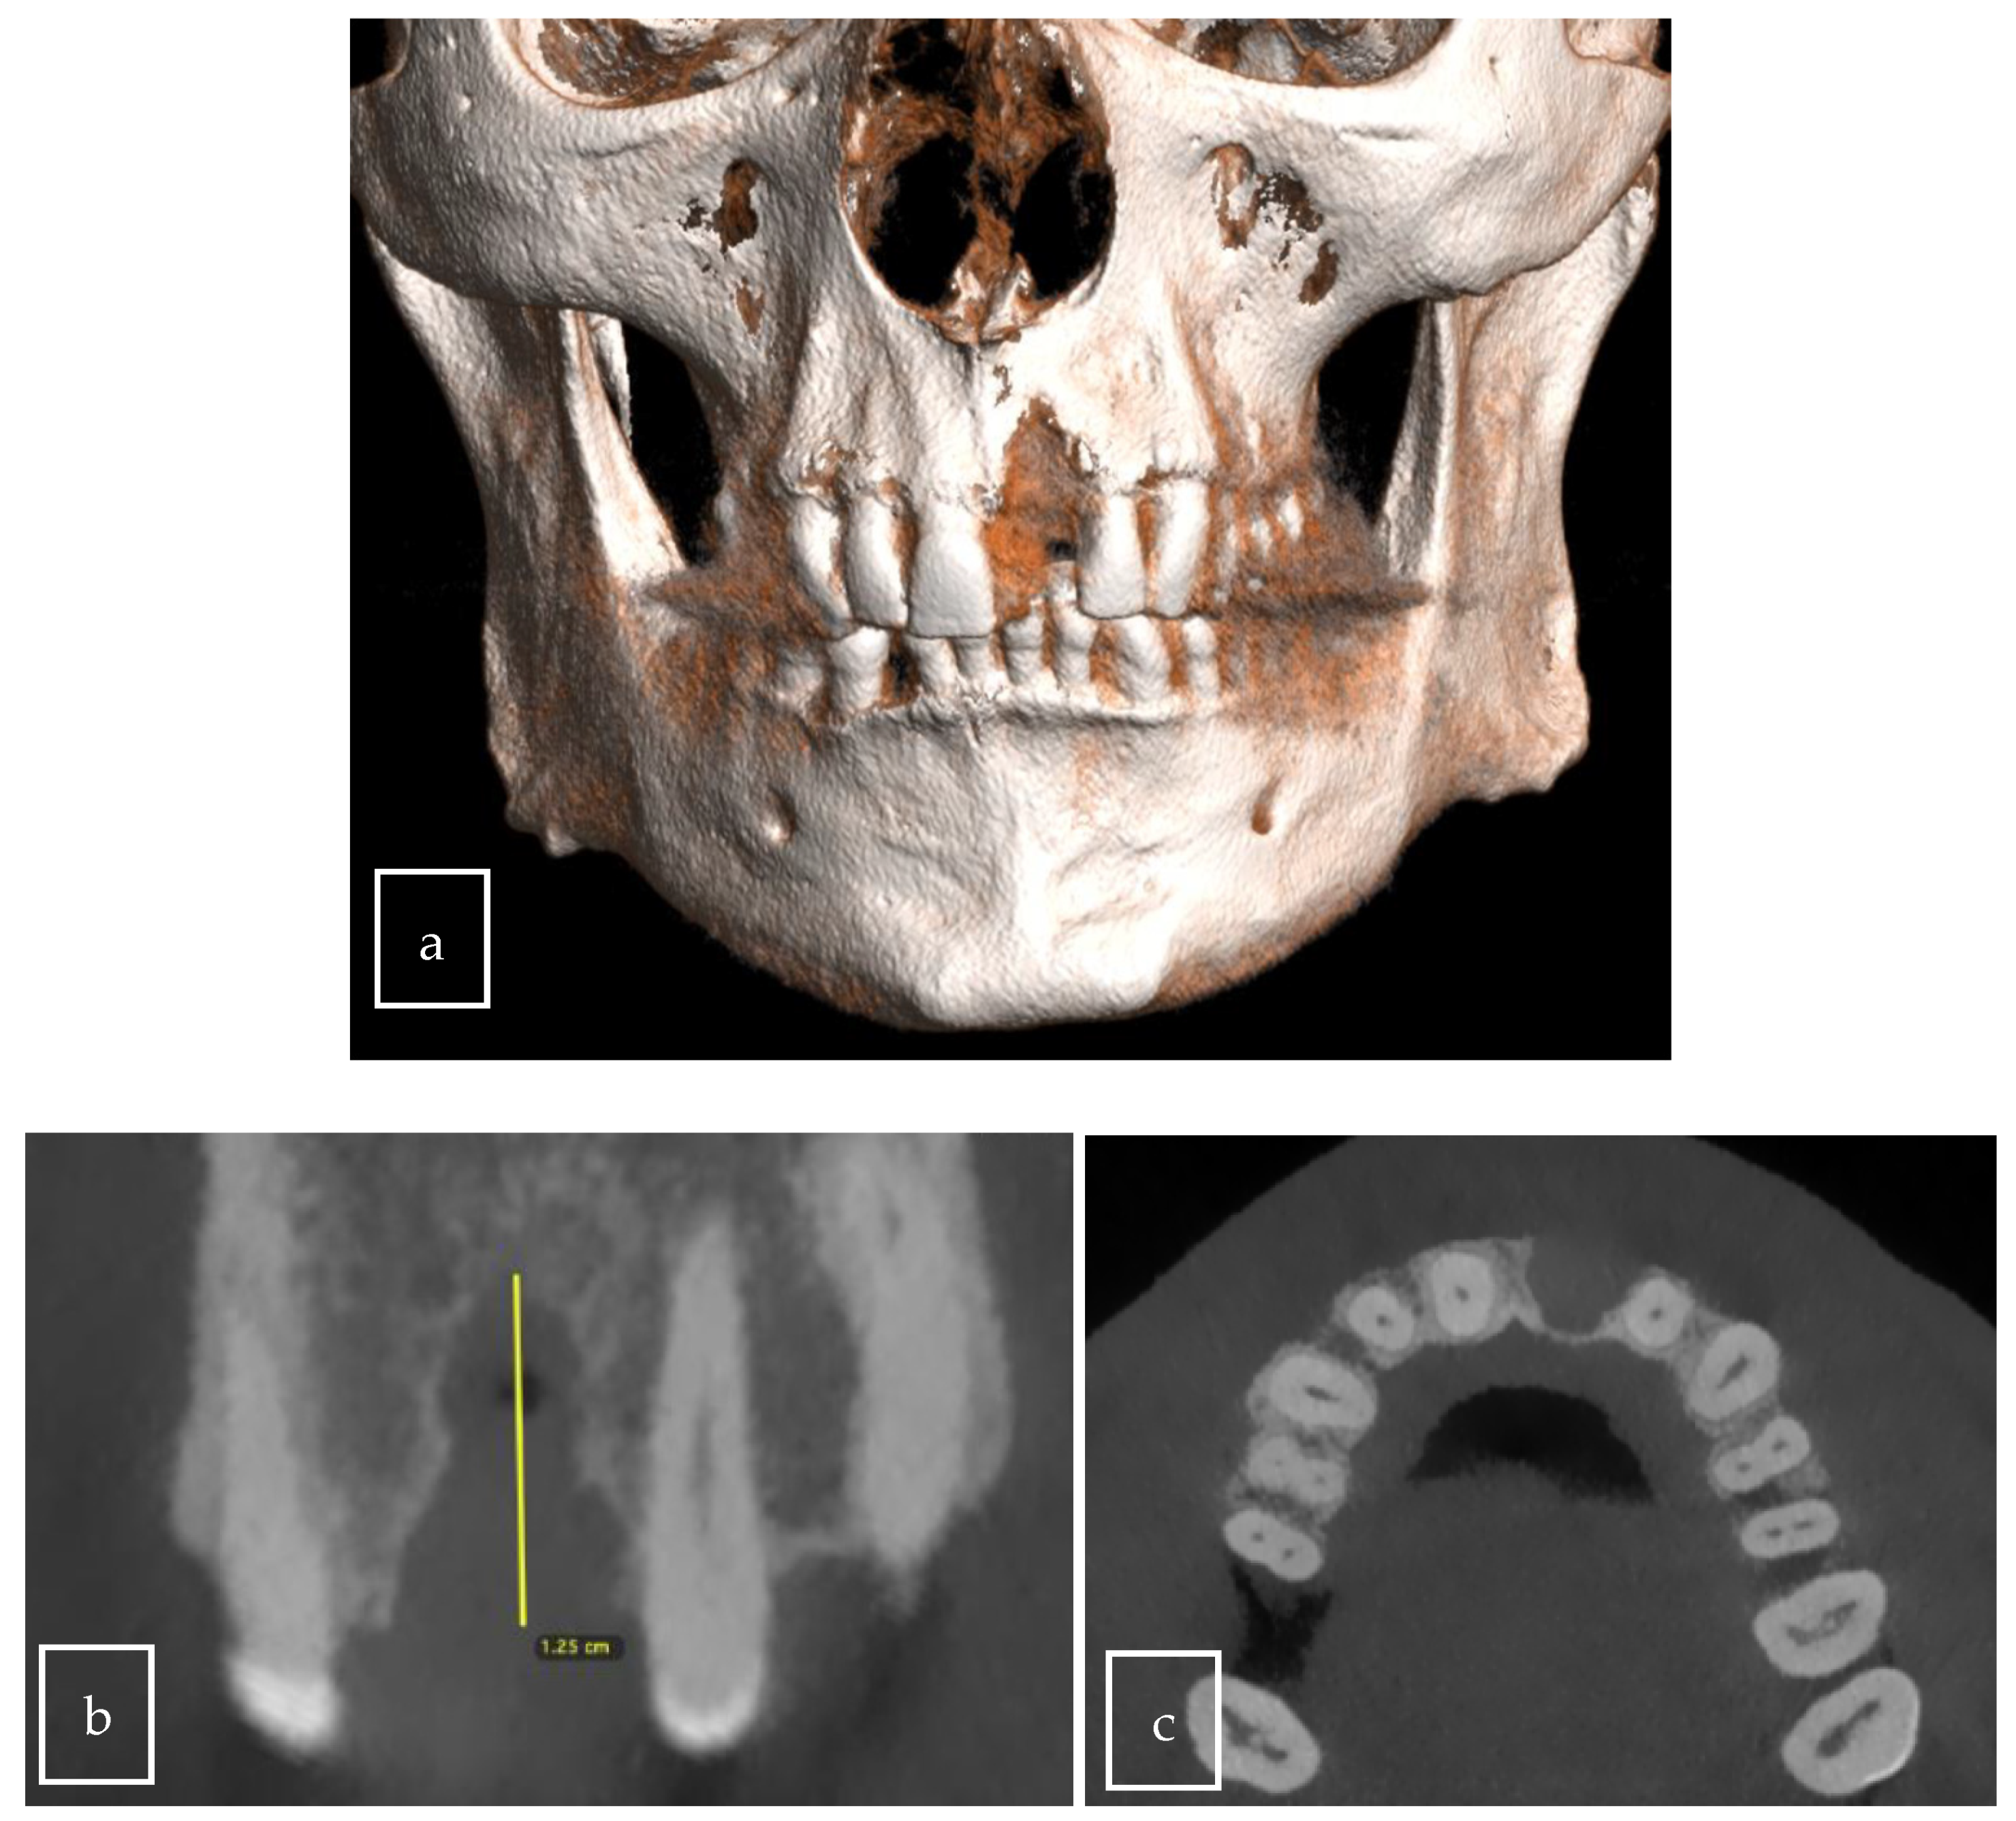

3.2. Case Presentation

| Our case | Case report | 1 | M | 63 | Asymptomatic | Right palate | Surgical excision | 9 × 8 × 12.5 mm | Radiolucent |